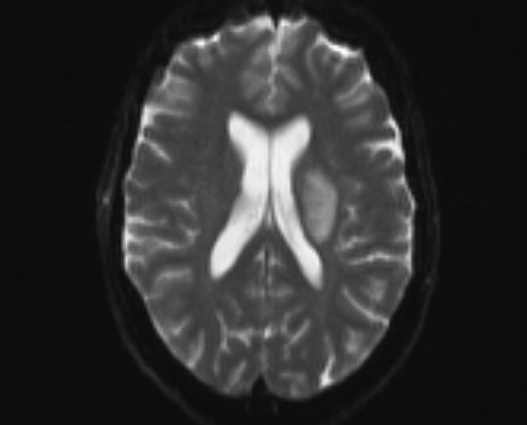

55-year-old female was admitted to our inpatient unit for neurological rehabilitation following stroke. Examination revealed right sided hemiparesis with power of 0/5 in upper limb and 2/5 in lower limb. Laboratory investigations were normal. Her lipid profile was raised. She also had an unremarkable 24-hour electrocardiogram and carotid Doppler. Brain Computed tomography and MRI scans showed left basal ganglia infarct. She was treated as an acute ischaemic stroke and commenced on rehabilitation. She was transferred to our unit to continue her neurological rehabilitation which was progressing slowly (Figure 1a –1c­­).

Figure 1b Magnetic resonance imaging showing left basal ganglia infarct.